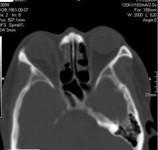

眼眶骨折

628健康网为您分享有关眼眶骨折的症状,眼眶骨折的治疗方法,眼眶骨折的预防知识,眼眶骨折的症状图片,眼眶骨折吃什么药,眼...

眼眶击出性骨折

628健康网为您分享有关眼眶击出性骨折的症状,眼眶击出性骨折的治疗方法,眼眶击出性骨折的预防知识,眼眶击出性骨折的症状...